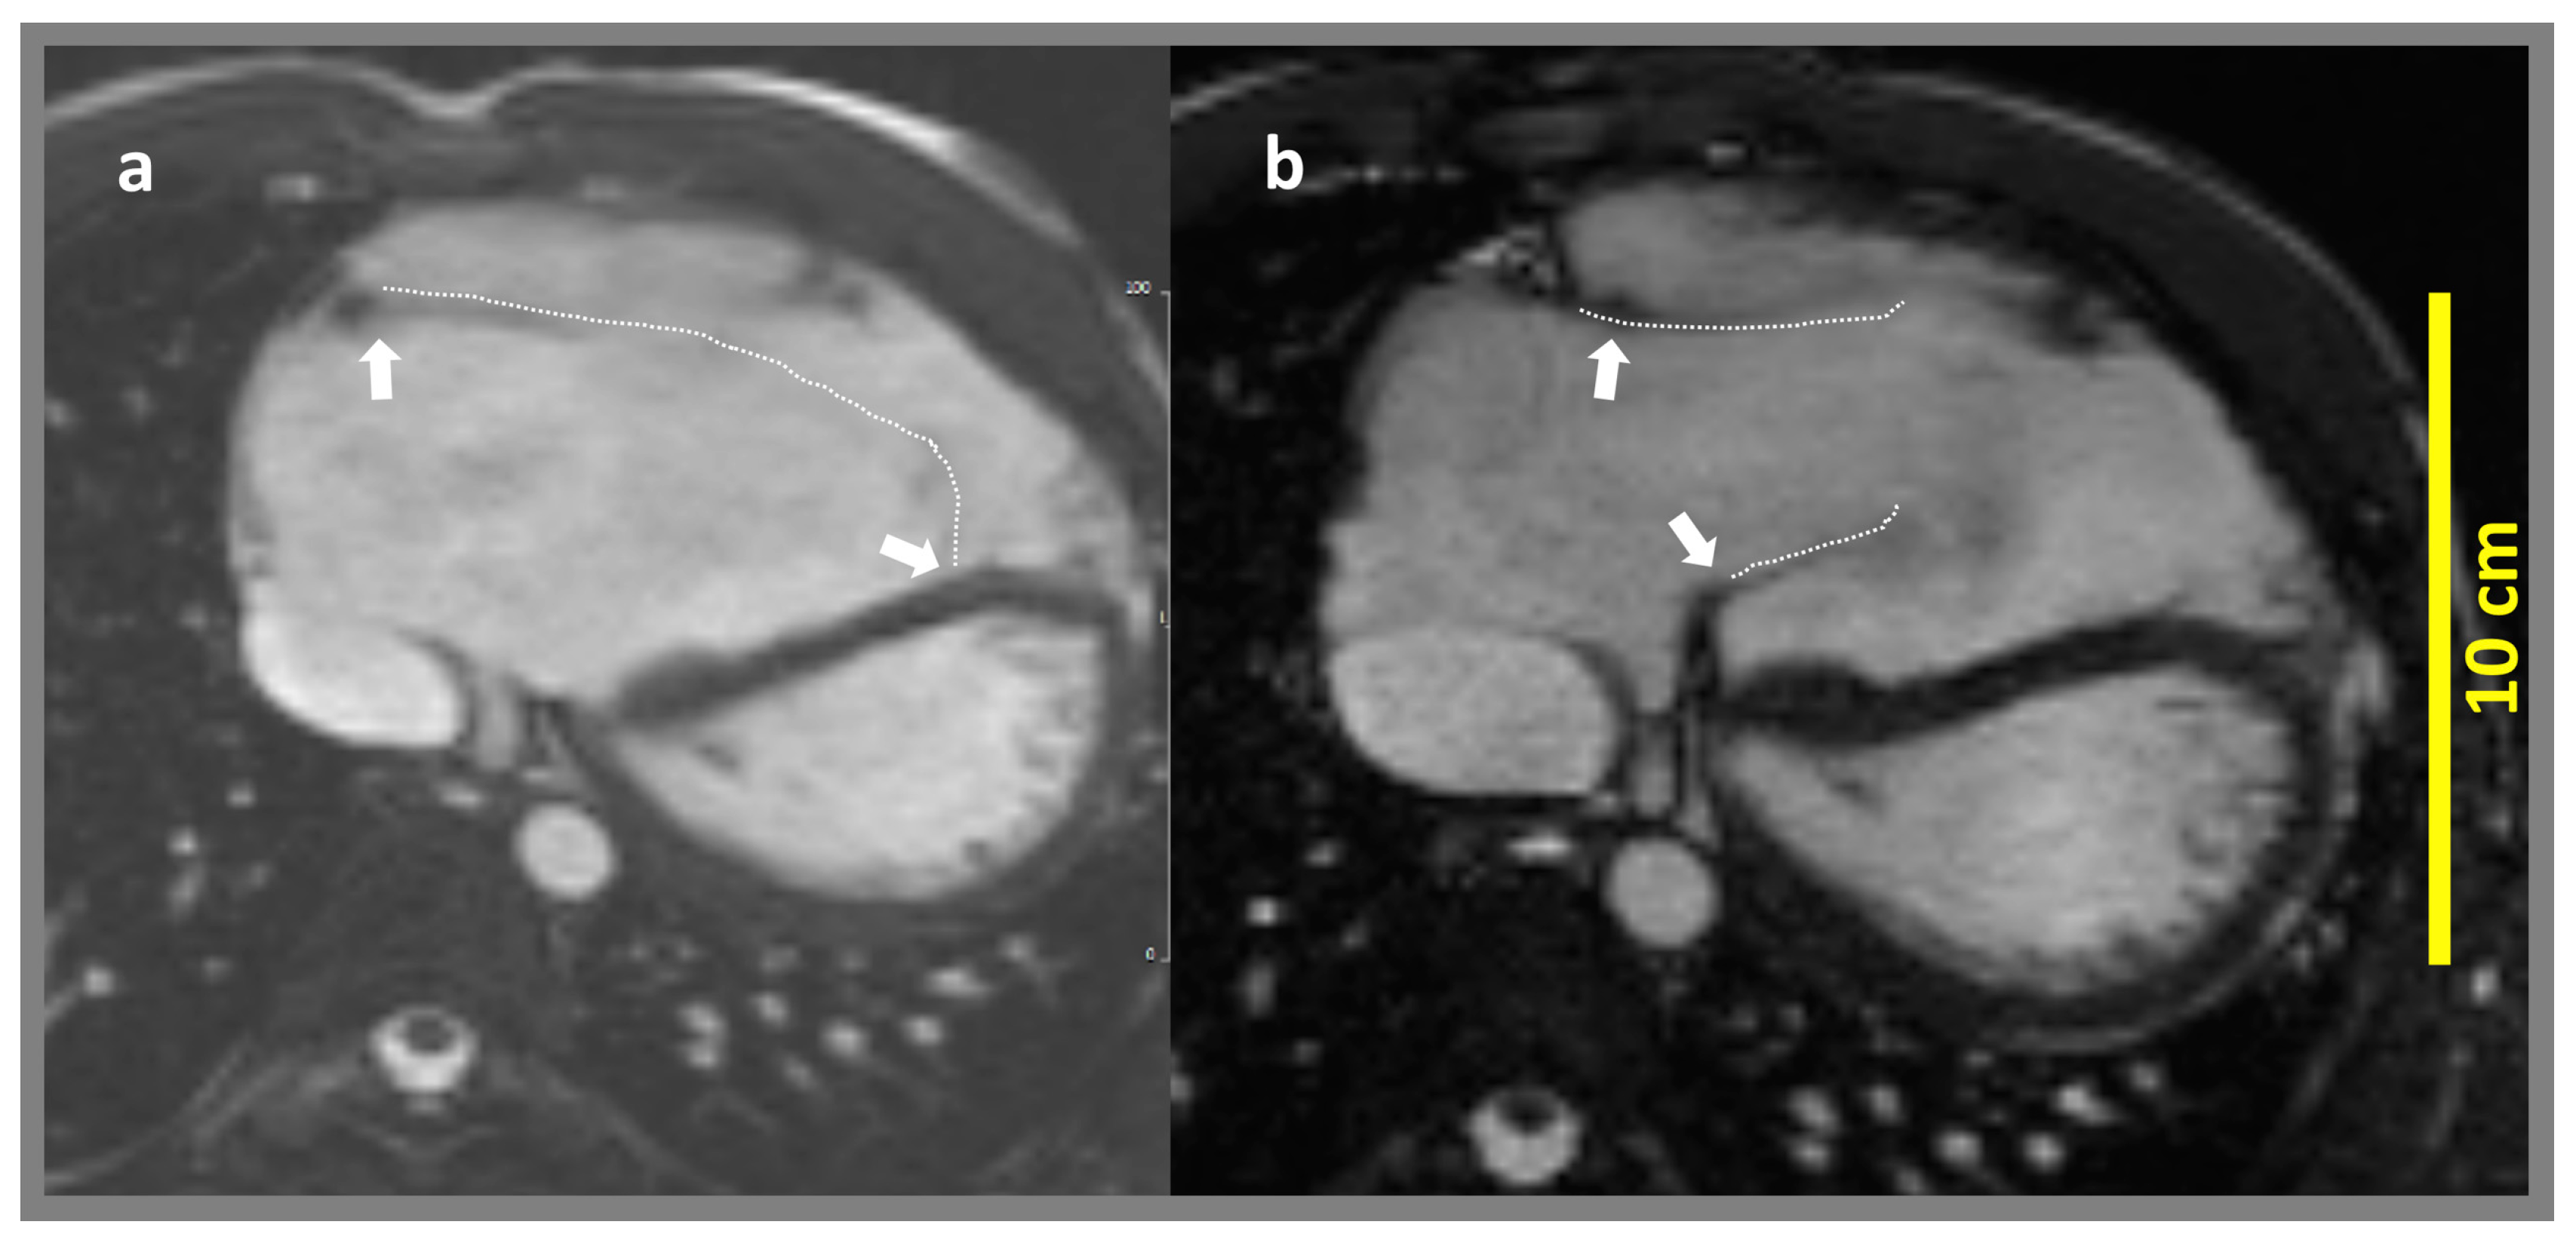

4.1. Impact of Cone Repair on Right Ventricular Volumes

4.2. Role of CMR-FT in the Perioperative Assessment of Right Ventricular Function